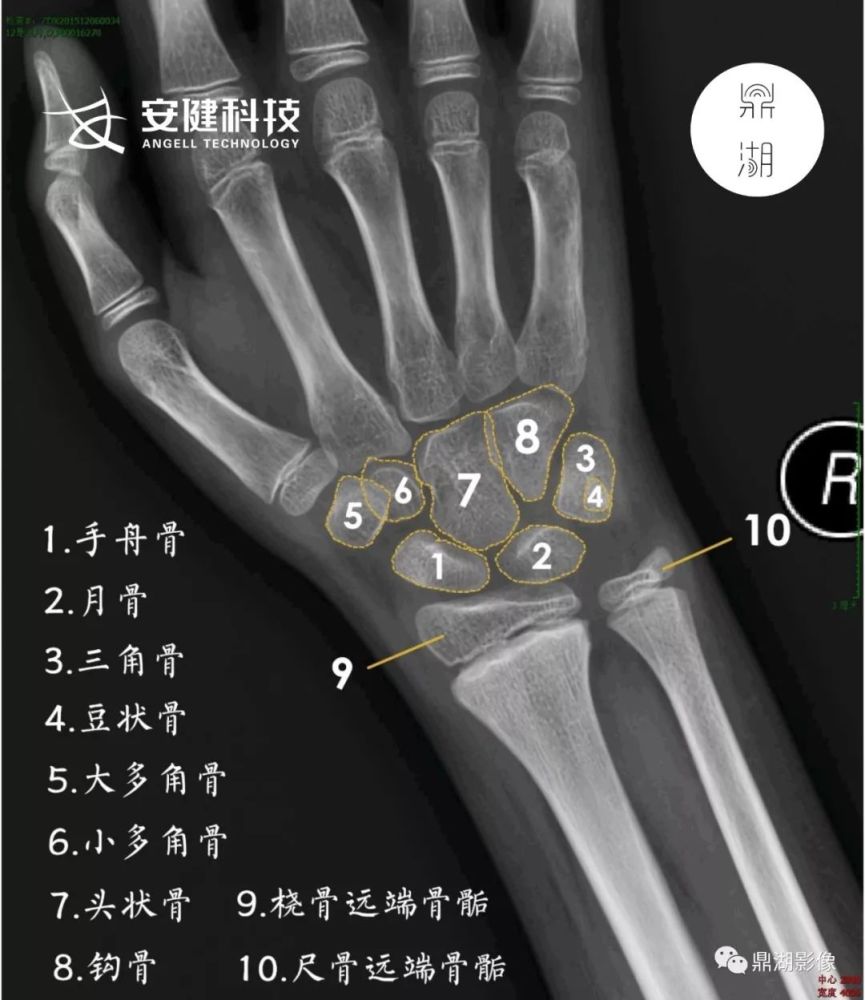

x线高清图谱精致腕关节解剖

正常腕关节x片图

正常腕关节x光片图片

腕关节x线图片

腕关节正常x片